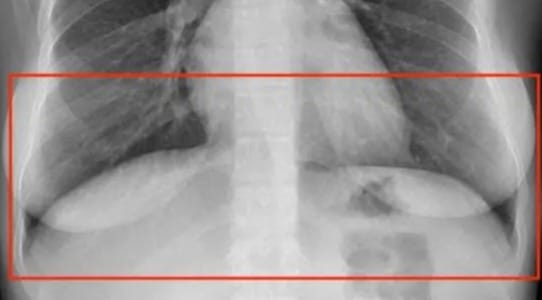

For example, occluded objects refer to objects partly visible in the image. As a rule of thumb, you should label them as if they were fully visible. But what if you can't differentiate them? Are the lower parts of the lungs behind or in front of the diaphragm?

The answer is both.